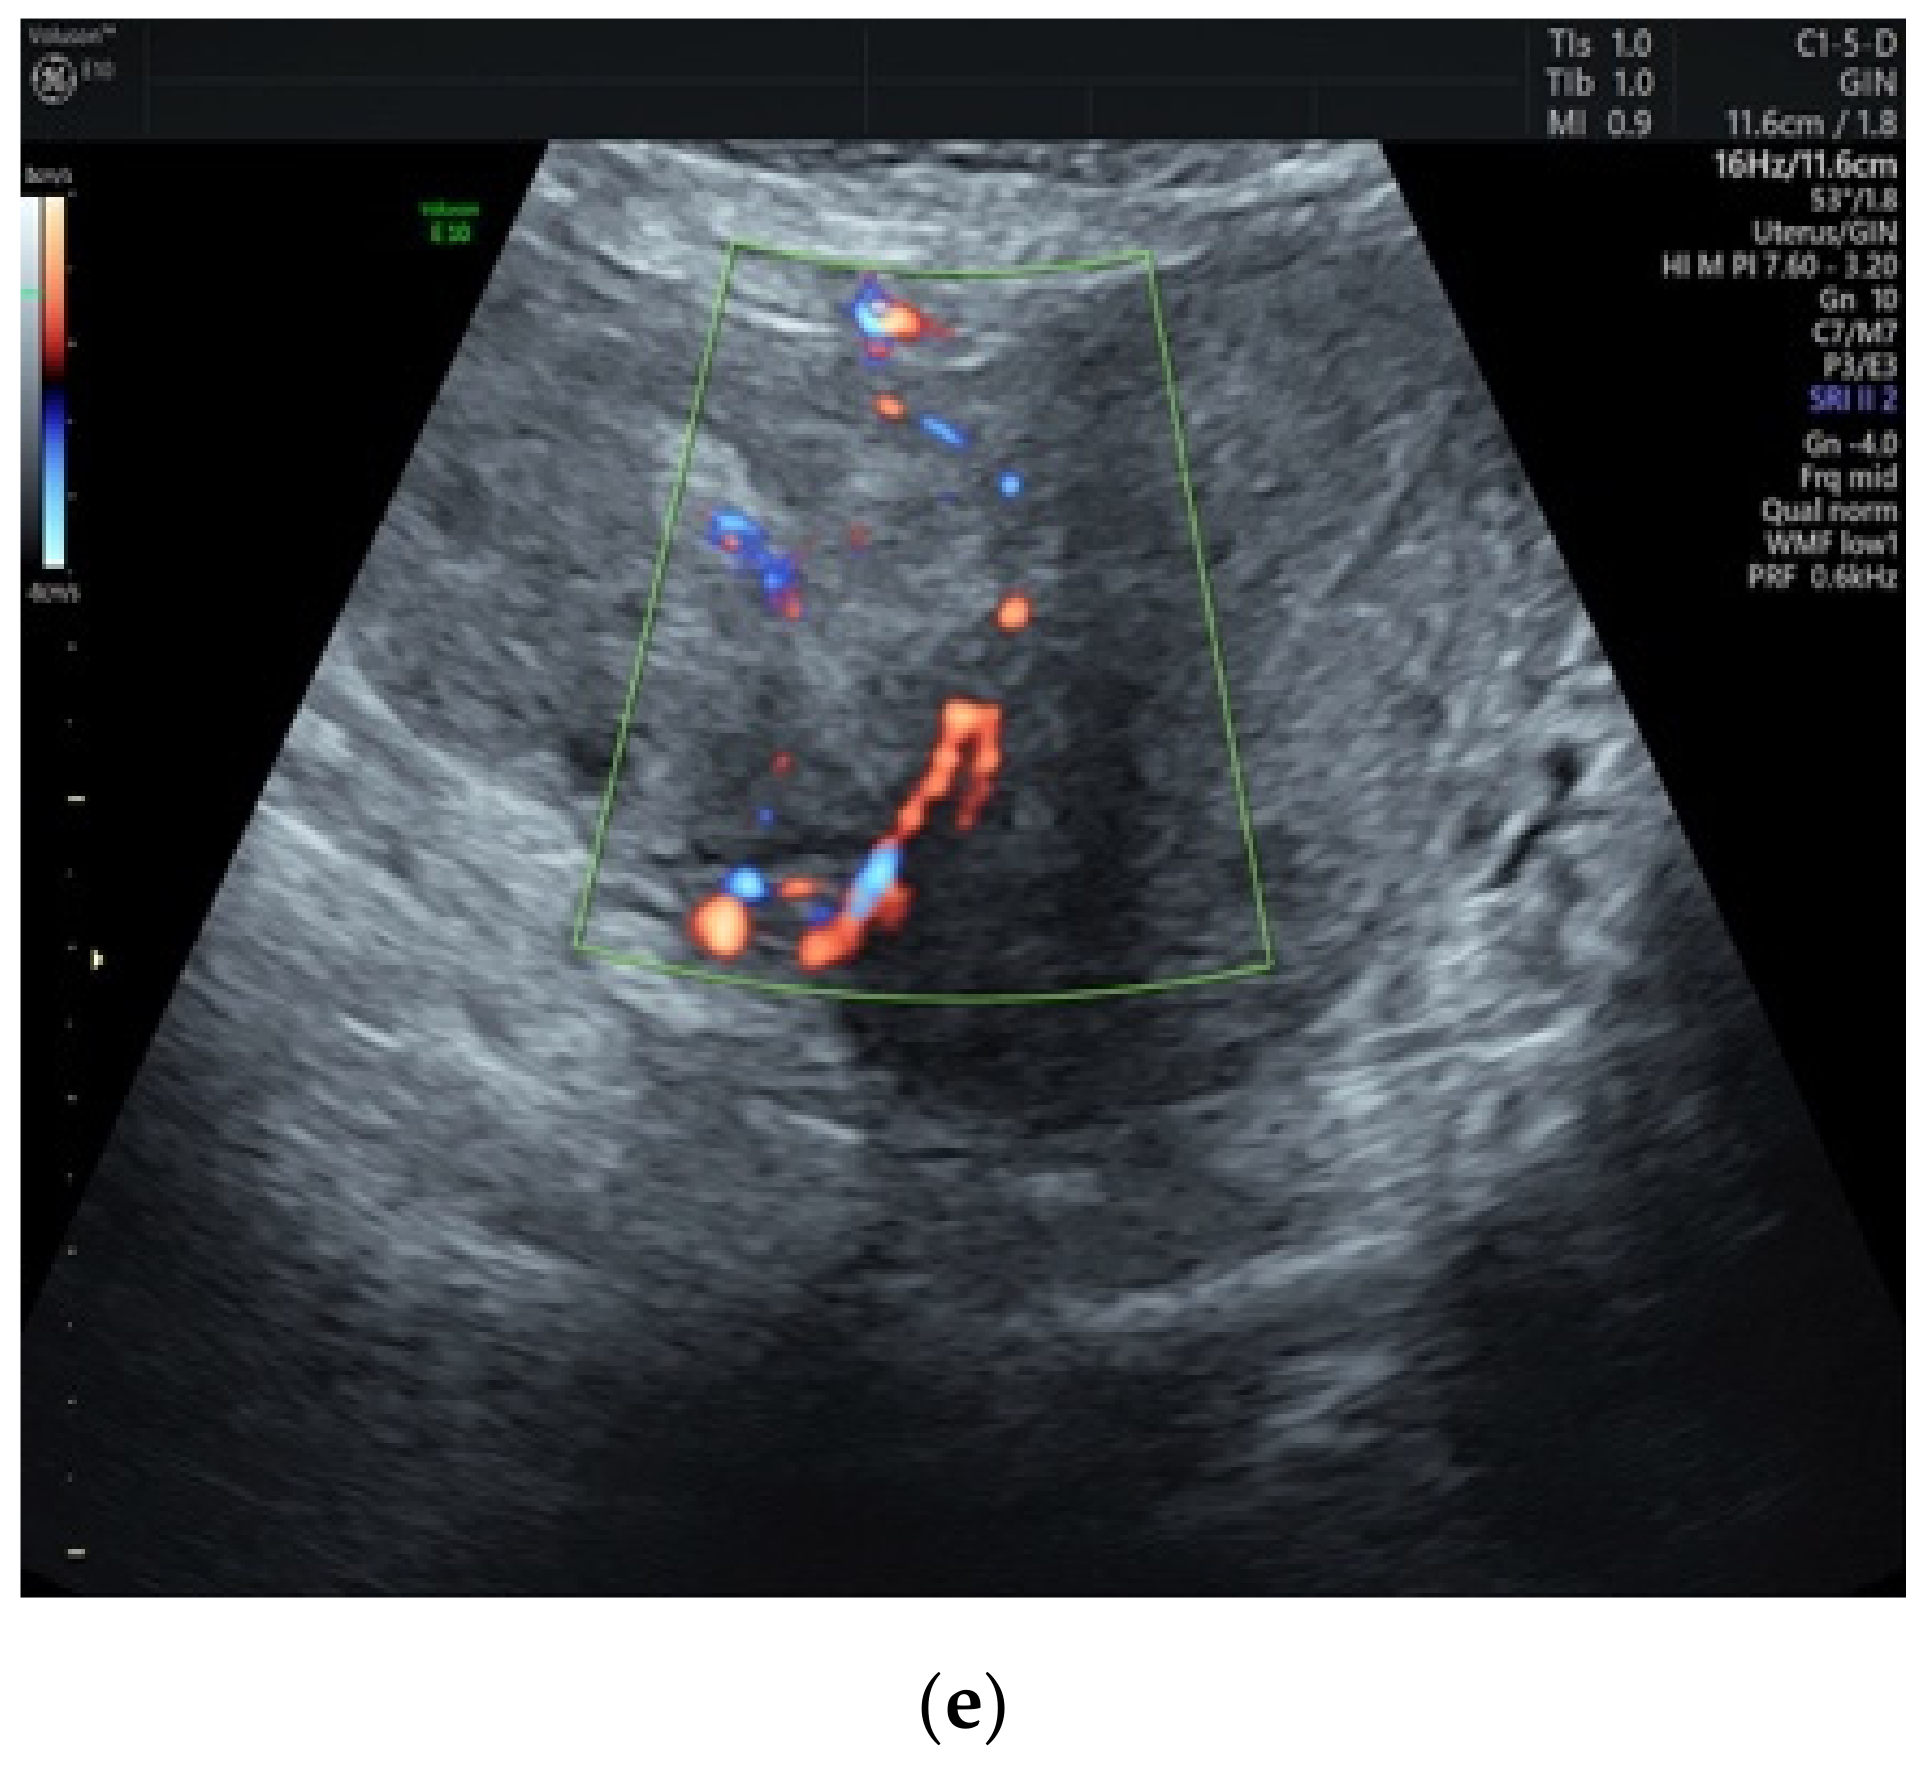

3.1. Preoperative Assessment